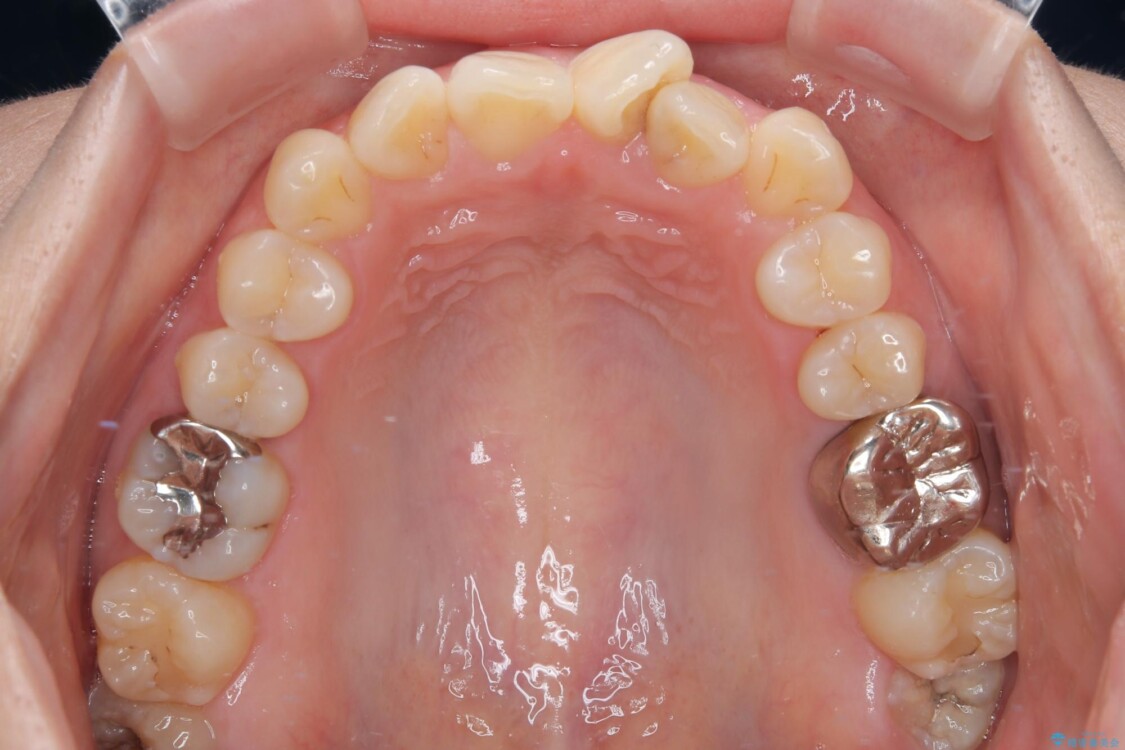

治療前

• 前歯のねじれ・ガタガタを10か月で改善!20代女性の矯正治療|クリアブラケットでむし歯になりにくい歯並びへ改善 治療前画像

診察の結果、上下の前歯部に**叢生(そうせい/歯のガタガタ・重なり)**が認められました。

特に上の前歯にはねじれや重なりがあり、審美的にも清掃性にも影響している状態でした。